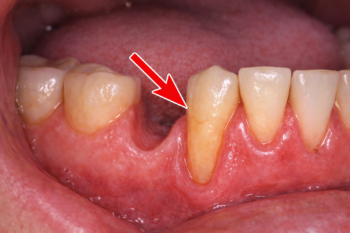

①歯周病

歯周病は、歯茎が下がる最も一般的な原因です。

歯と歯茎の境目に細菌がたまり炎症が起こることで、歯を支えている骨が徐々に溶けていきます。

骨が失われると、それに伴って歯茎も下がり、歯が長く見えるようになります。

初期は痛みが少なく気づきにくいため、知らないうちに進行しているケースも少なくありません。